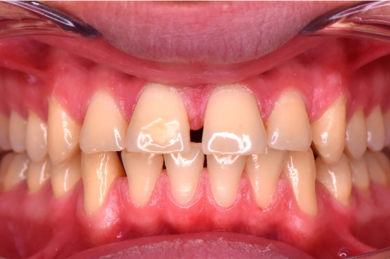

-  دندان ها روی هم قرار گرفته اند کج و نامرتب هستند. . زمانی رخ می دهد که فضای کافی برای رشد و نمو طبیعی دندان های دائمی وجود نداشته باشد.

-  بین دندانها فاصله است